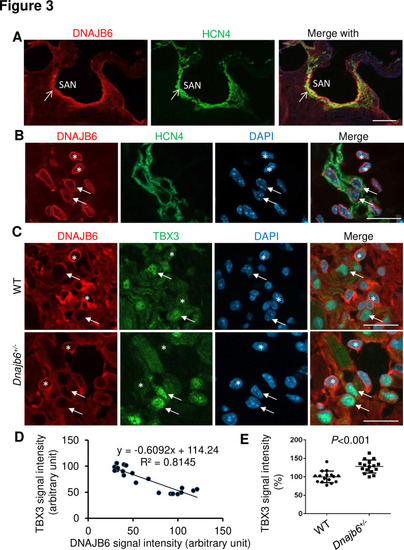

Expression and localization of DNAJB6 in the mouse SAN.(A) The anti-DNAJB6 antibody immunostaining signal largely overlapped with the HCN4 immunostaining signal in the mouse SAN tissues under low magnification. (B) Under higher magnification, expression of DNAJB6 (red) only partially overlapped with HCN4 (green) as revealed by antibody co-immunostaining. Arrows point to cells with overlapping patterns. Stars indicate cells with no-overlapping. (C) Shown are fluorescent images after DNAJB6 and TBX3 antibody co-immunostaining indicating expression of DNAJB6 protein in the WT versus Dnajb6+/- +/- mouse SAN. Arrows point to cells with weak DNAJB6 but strong TBX3 immunostaining signal. Stars indicate cells with strong DNAJB6 but low level of TBX3 immunostaining signal. (D) Quantification and correlation analysis of DNAJB6 and TBX3 immunostaining signal in WT SAN. (E) Quantification analysis of TBX3 signal in the WT versus Dnajb6+/- mouse SAN. N=20 cells. Unpaired student’s t-test. Scale bars in A, 50 µm; In B, C, D, 20 µm. |